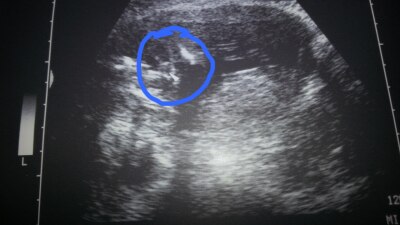

Hallo Mädels Hatte heute wieder einen arzt termin. Dem kleinen gehts super und alles ok.er liegt komplett auf der linken Seite, und da spüre ich auch die zarten bewegungen.Anbei das outing bild hoffe ihr könnt es erkennen. Haben ja schon vor vier Wochen unser outing bei der frühdiagnostik bekommen und mein arzt hat es heut nochmals bestätigt.  Schöne grüße verena

Bild zu zurück vom FA-termin - Forum für November - Mamis